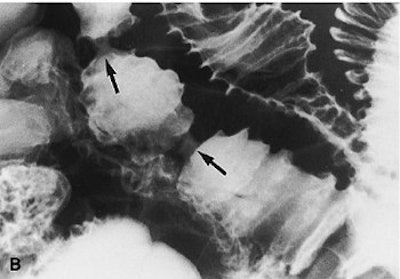

![]() ![]() |

Overhead view (A) shows three abnormal jejunal loops. Four broad-based strictures with lumps are seen in loop 2 (arrows). Compression spot view of loops 1-2 (B). Marked luminal narrowing in two of the four strictures in loop 2 (arrows) is seen with a resultant life-saver or bagel-like configuration. Compression spot view of loop 3 (C). Multiple ring or diaphragm-like strictures (arrows) and broader-based strictures (arrowheads) are evident. Images courtesy of the Canadian Association of Radiologists (Abdominal Imaging, 1998; 23:40-44).